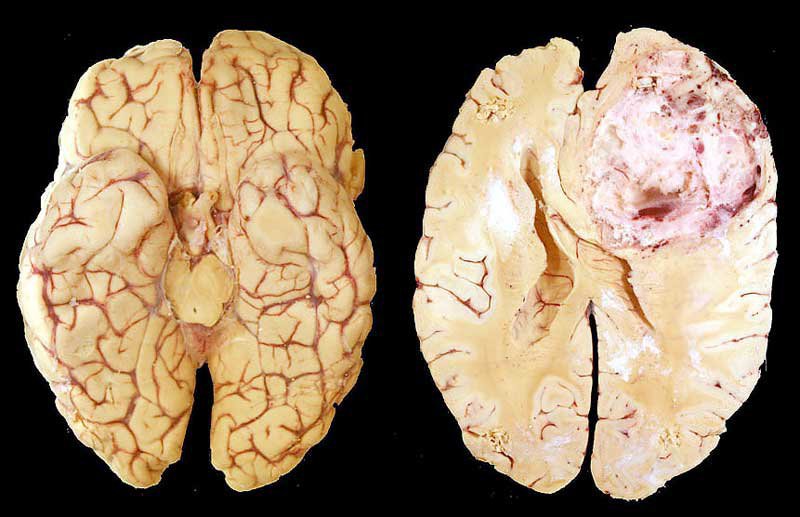

Chẩn đoán u nguyên bào thần kinh đệm được xác định bằng cách sử dụng các phương pháp chẩn đoán hình ảnh như MRI, CT scan và xét nghiệm tế bào u. MRI là phương pháp chẩn đoán tốt nhất để xác định u nguyên bào thần kinh đệm.

Điều trị bao gồm phẫu thuật, xạ trị, và hóa trị liệu để giảm thể tích khối u. Phẫu thuật là phương thức điều trị ban đầu phổ biến nhất đối với u thần kinh đệm, và đòi hỏi phẫu thuật mở hộp sọ. Việc cắt bỏ một cách an toàn càng nhiều khối u càng tốt (không gây tổn hại quá mức đến). Ngoài ra, điều trị còn bao gồm xạ trị và hóa trị liệu để giảm thể tích khối u. Tuy nhiên, điều trị u nguyên bào thần kinh đệm đa dạng thường không thể loại bỏ hoàn toàn khối u.